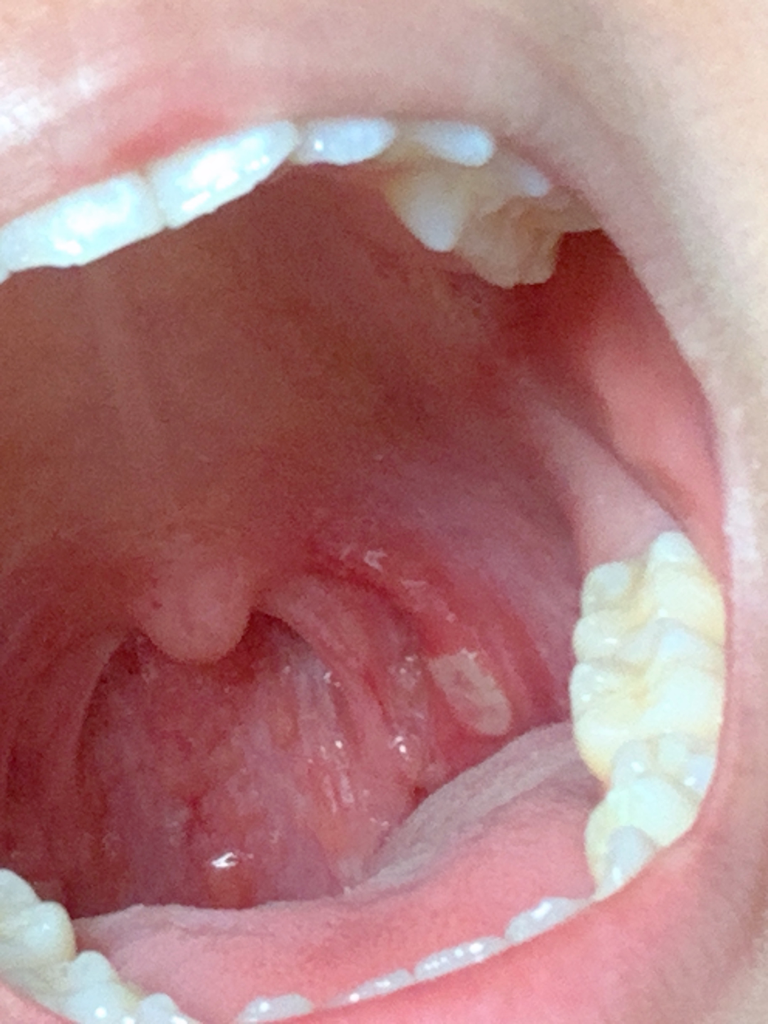

사진의 소견을 통해서 보았을 때에는 단순 아프타성 구내염일 가능성이 높아 보입니다. 아프타 구내염은 특별히 몸에 이상이 있는 것은 아니며 몸의 컨디션 및 면역력이 저하될 경우 자연스럽게 발생할 수 있는 증상입니다. 따로 약물 복용이 필요한 것은 아니며 컨디션을 잘 관리하면서 회복하면 자연스럽게 좋아지겠습니다. 스테로이드 사용이 회복을 촉진할 수 있지만 반드시 필요한 것은 아니며 스테로이드 약물은 남용할 경우 부작용의 위험이 커서 추천드리는 방법은 아닙니다. 알보칠 같은 약물을 발라보는 것도 시도해볼 수 있으나 질병의 경과를 크게 바꾸지는 못한다고 합니다.